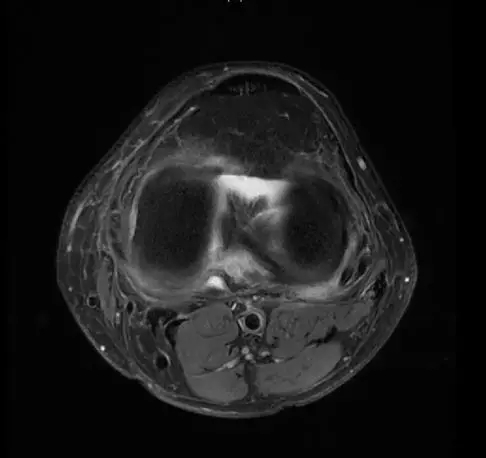

后交叉韧带断裂

从此片可以看出后交叉韧带连续性中断,松弛,增粗,下止点信号增高比较明显,从这个角度看后交叉韧带上止点信号较为正常,但下止点信号明显增高,缺乏韧带止点应有的形态,从这个层面看下止点信号增高,从这个层面看韧带是增粗的,整体信号增高,质地不均一,并且松弛,从这个层面可以看到它的下止点信号增高,缺乏正常的韧带形态特点,所以考虑后交叉韧带断裂。